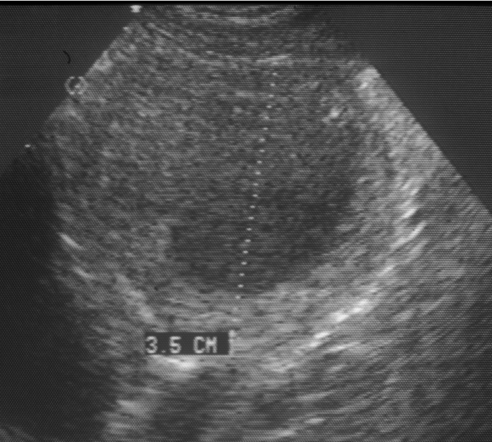

3 characteristics of prostate ultrasound during prostatitis

Appears multiloculated (multiple chambers)

Flocculant (cloudy), anechoic (black) fluid

Large hyperechoic capsule